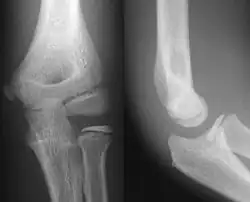

- Elbow - AP and Lateral. Radial head projections available on request

-

Lateral projection -

Anteroposterior projection -

Left elbow by 30 degrees internal oblique projection -

Left elbow by 30 degrees external oblique projection

- Soft tissues are seen with the same machine as for hard tissues, but a "softer" or less-penetrating X-ray beam is used. Tissues commonly imaged include the lungs and heart shadow in a chest X-ray, the air pattern of the bowel in abdominal X-rays, the soft tissues of the neck, the orbits by a skull X-ray before an MRI to check for radiopaque foreign bodies (especially metal), and of course the soft tissue shadows in X-rays of bony injuries are looked at by the radiologist for signs of hidden trauma (for example, the famous "fat pad" sign on a fractured elbow).